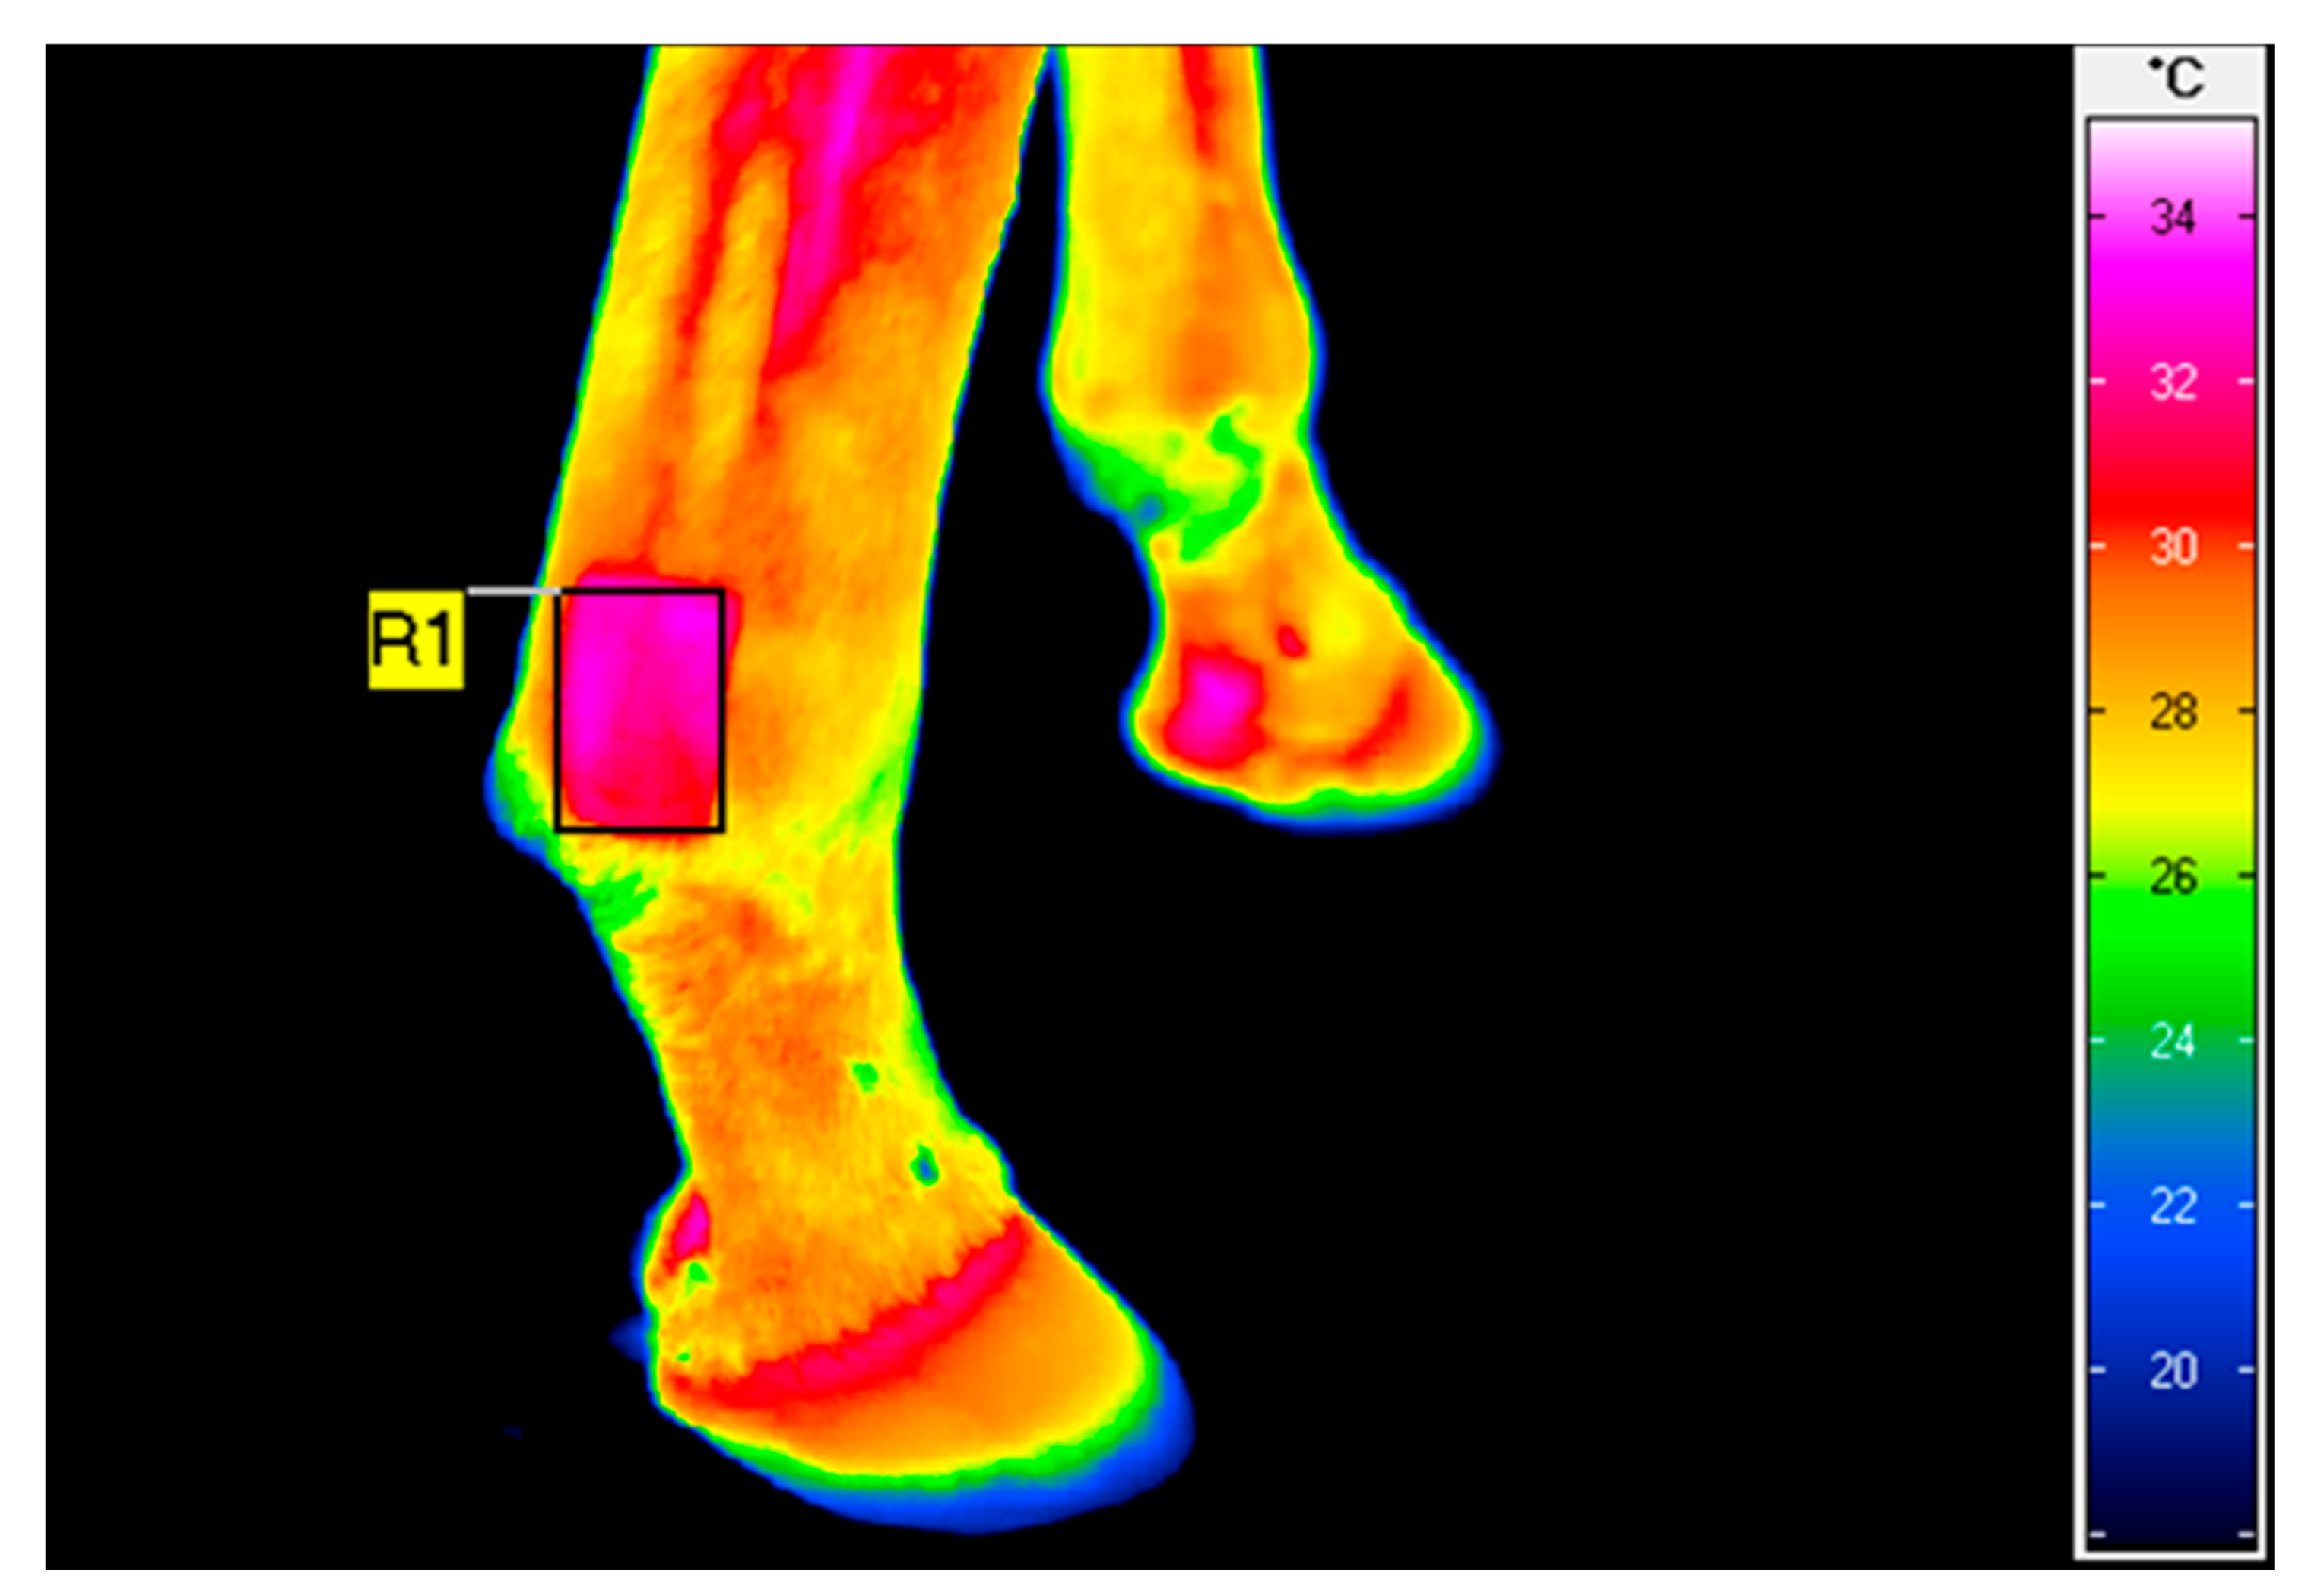

2.2. Thermography

Skin Surface Temperature and Vein Diameter